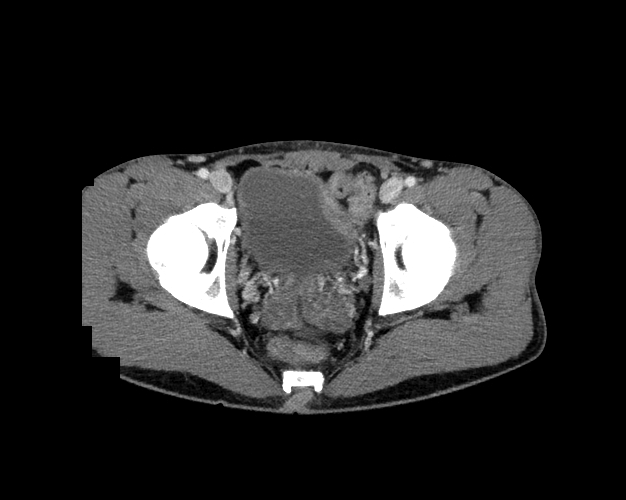

Body

Covers abdominal CT anatomy.